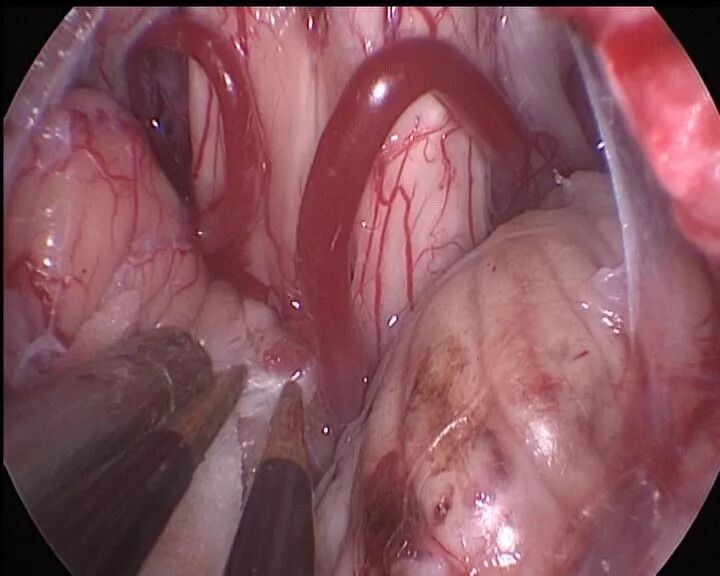

手术图像

抬起小脑蚓,暴露并剪开蛛网膜小梁

电凝一侧小脑蚓部使之回缩

抬起对侧小脑蚓,剪开蛛网膜小梁

分离对侧小脑蚓和PICA的粘连

分离小脑谷,寻找四脑室正中孔

暴露四脑室正中孔,可见增厚的脉络膜

明胶海绵放入正中孔,分隔脑干和脉络膜

电凝并切开增厚的脉络膜

完全开放四脑室正中孔